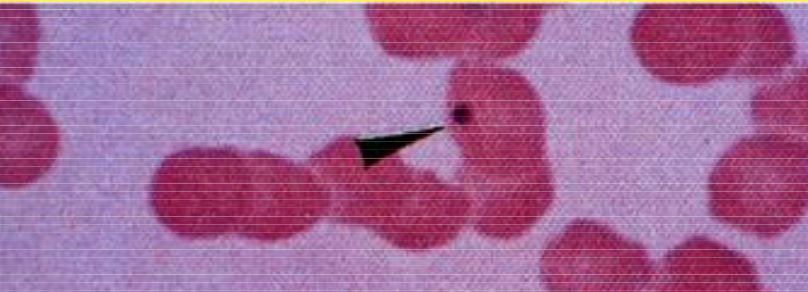

What is shown in this picture (overall and black arrowhead)?

A

Rouleaux

Howel Jolly Bodies (arrowhead)